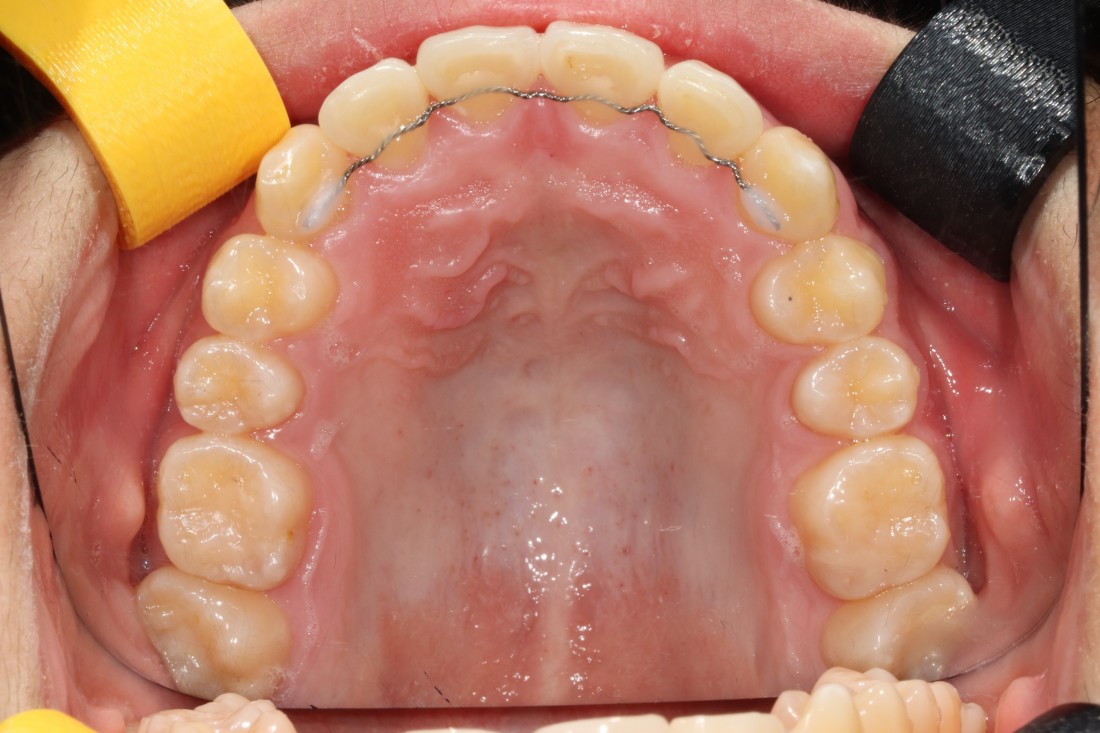

광주 덧니교정 치과는

대표원장인 제가 직접

다양한 교정 전/후 케이스를

공유하고 있습니다.

다양한 각도에서 촬영한

교정 전/후 사진을 직접 확인할 수 있어

광주 덧니교정 치과의

실력있는 진료를 증명하고 있습니다.

발치를 진행한 덧니교정이나

비발치 덧니교정 모두

다양한 케이스를 보유하고 있기 때문에

나의 구강구조와 비교해보면서

성공적인 교정치료 결과를

기대해보실 수 있습니다.